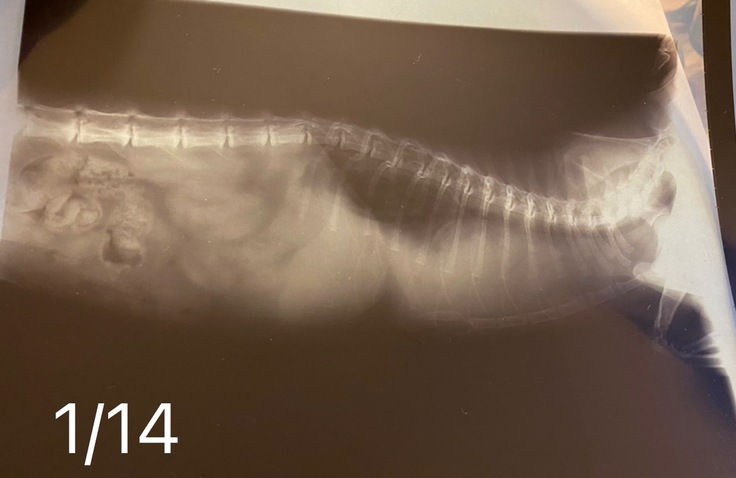

1/14(土)

朝一番に病院に行く用意をしていると

呼吸のたびに鼻をピクピクさせるように。。

【鼻翼呼吸】

すぐにネットで調べると

かなり苦しい状態とのこと。

かかりつけの病院へ急ぎました。

レントゲンやエコーの検査をしました。

『肺も心臓も真っ白で、何も写っていない。

かなり悪い状態です。

今日か明日亡くなる可能性が高い。。。

この週末で何が起きるかわからない。

これは簡単に治るような病気じゃない。

胸水の量が多いし、

空気も取り込めてないですよ。

鎮静剤を使って胸水の検査をしてもいいけど

こんな状態だから

そのまま起きない可能性が高い。』

↓どちらの動物病院からも↓

掲載許可を得ています

『黄色い胸水、

血液検査などの結果から

FIPの可能性が高いです。

治療から5日目(1/20)にも胸水を75ml抜いてもらいましたが

やはり日ごとに呼吸が早くなるので

1/29、31とレントゲンで胸水の確認もしてもらっています。